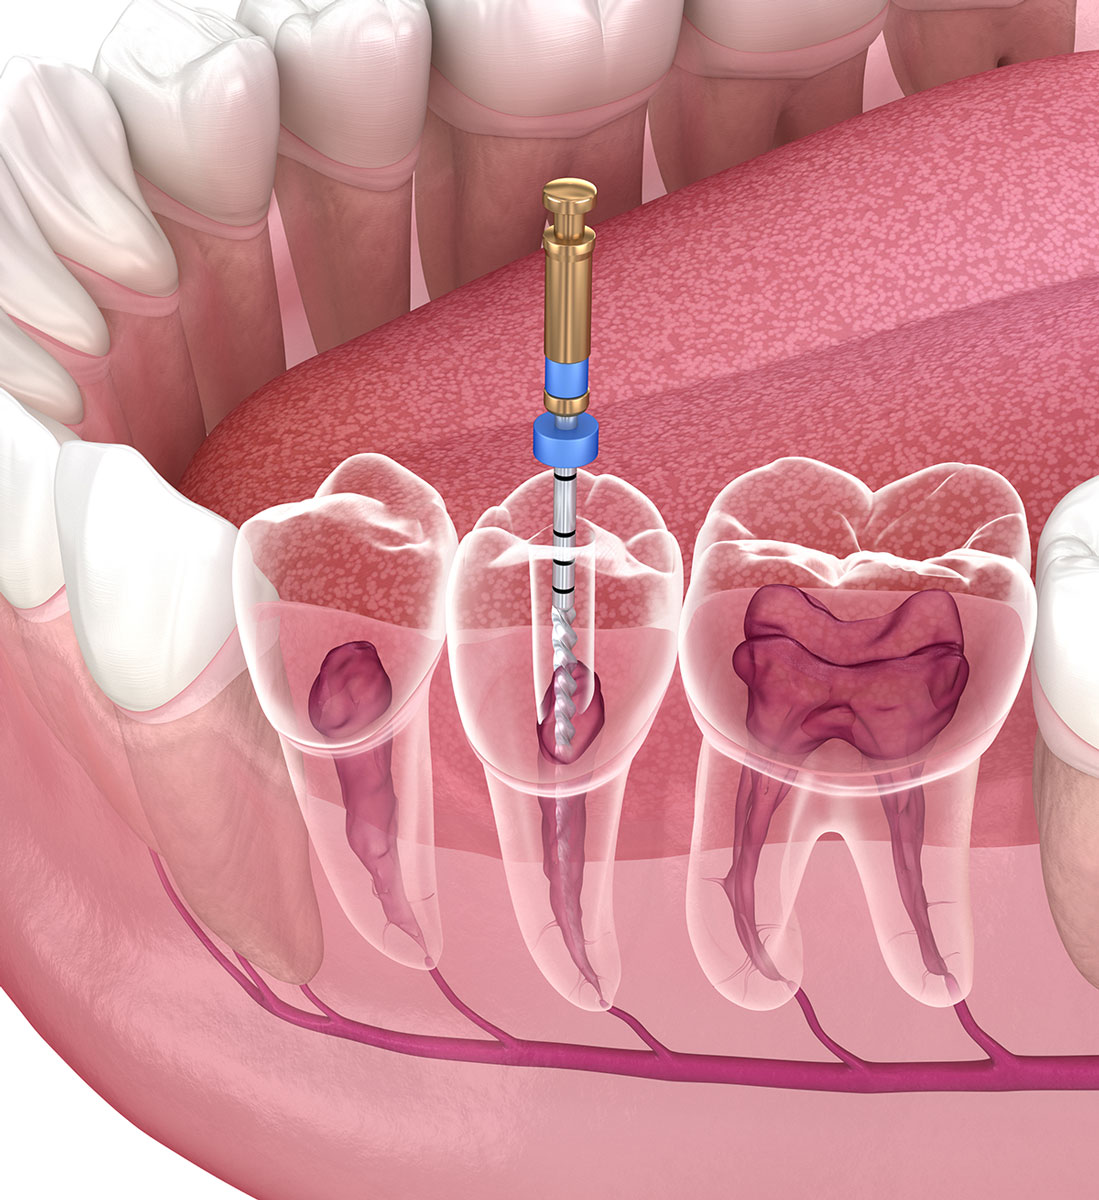

Quando ricorrere alla devitalizzazione del dente

La cura canalare è il metodo con cui si devitalizzano i denti affetti da patologie infiammatorie che aggrediscono la polpa dentale o le radici. Lo scopo è eliminare il tessuto pulpare infetto per preservare la parte dura e sana del dente. Il trattamento si rende necessario in presenza di:

- Granulomi

- Carie profonde

- Traumi dentali

- Pulpiti e necrosi pulpari